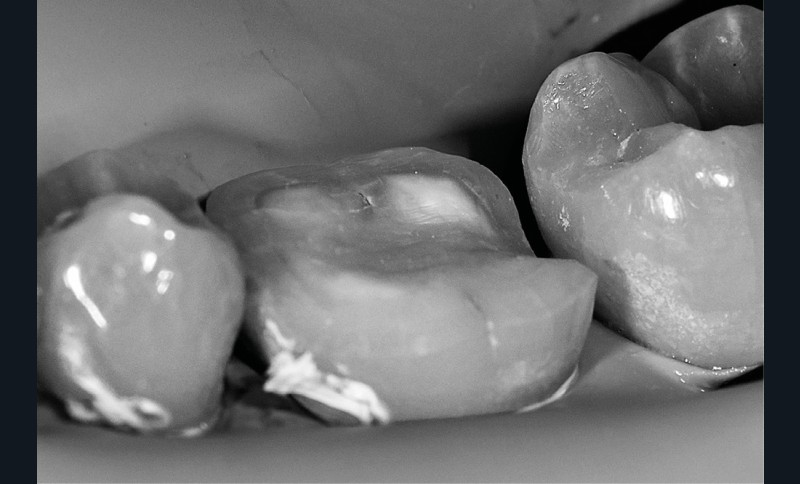

La procédure clinique est construite en deux séances. Lors de la première séance, d’une durée de 3 h, nous effectuons l’endodontie, la base intermédiaire, la préparation de l’overlay, et l’empreinte optique. La cavité d’accès réalisée est aussi petite que possible, mais aussi large que nécessaire afin de favoriser un maximum de préservation tissulaire tout en permettant un accès raisonnable aux canaux (fig. 2).

Une partie de la crête marginale distale est éliminée pour traiter la fissure. Une reconstruction pré-endodontique définitive est préférable à ce stade, afin de maximiser les valeurs d’adhérence du composite en évitant les contaminants endodontiques (fig. 3).